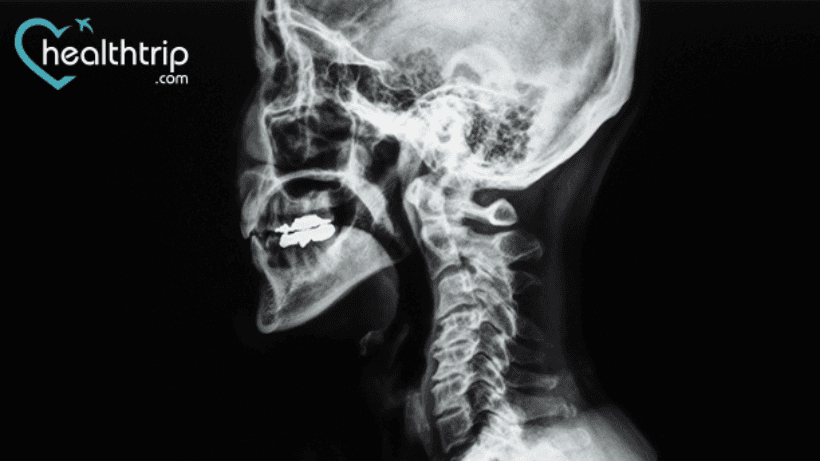

Operasi diskektomi dan fusi serviks anterior (ACDF) dilakukan di leher Anda untuk mengangkat cakram atau taji tulang yang rusak. Dan jika Anda penasaran berapa tahun hasil operasi tersebut bertahan, Anda berada di halaman yang tepat. Di sini kami telah membahas secara singkat tingkat keberhasilannya dan fakta lain yang perlu Anda ketahui setelah menjalaninya perawatan medis.

ACDF meningkatkan hasil untuk semua diagnosis primer dan telah terbukti bertahan selama lebih dari sepuluh tahun. Operasi sekunder dilakukan untuk memperbaiki pseudarthrosis dan untuk mengobati degenerasi level yang berdekatan simtomatik.

Operasi ini sangat sukses. Orang yang menjalani operasi ACDF untuk nyeri lengan melaporkan pereda nyeri pada 93 hingga 100 persen kasus, dan orang yang menjalani operasi ACDF untuk nyeri leher melaporkan hasil positif pada 73 hingga 83 persen kasus.